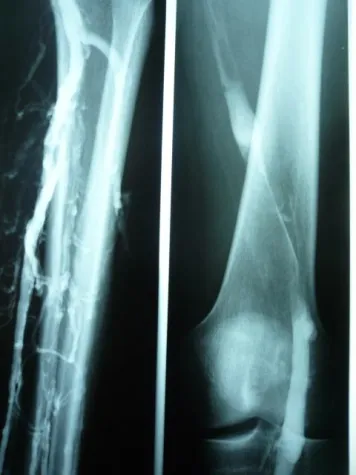

Ist jedoch die Kniekehlenvene nach Thrombose verschlossen , fliesst kein Blut mehr aus dem Bein,oder wird stark behindert. Lebenslanger Stau ist die Folge bis hin zum Offenen Bein. Das Vollbild des Postthrombotischen Syndroms ist erreicht : Schwere-und Spannungsgefühl,Juckreiz , Ödeme, Ekzeme,Bestungsschmerz , Allergien auf diverse" Venensalben", Krampfaderbildung führen dann bei oft banaler Verletzung zum Ulcus cruris -dem gefürchteten Beingeschwür.Mythen behaftet.

Nur man muss so früh wie möglich damit beginnen ! Aber es stimmt wohl nicht , dass nach 10 Tagen kein Erfolg mehr zu erzielen ist : auch wenn die Thrombose schon 4-6 Wochen zurückliegt gelingt es eine fest verschlossene Kniekehlenven und Oberschenkelvene zu eröffnen .